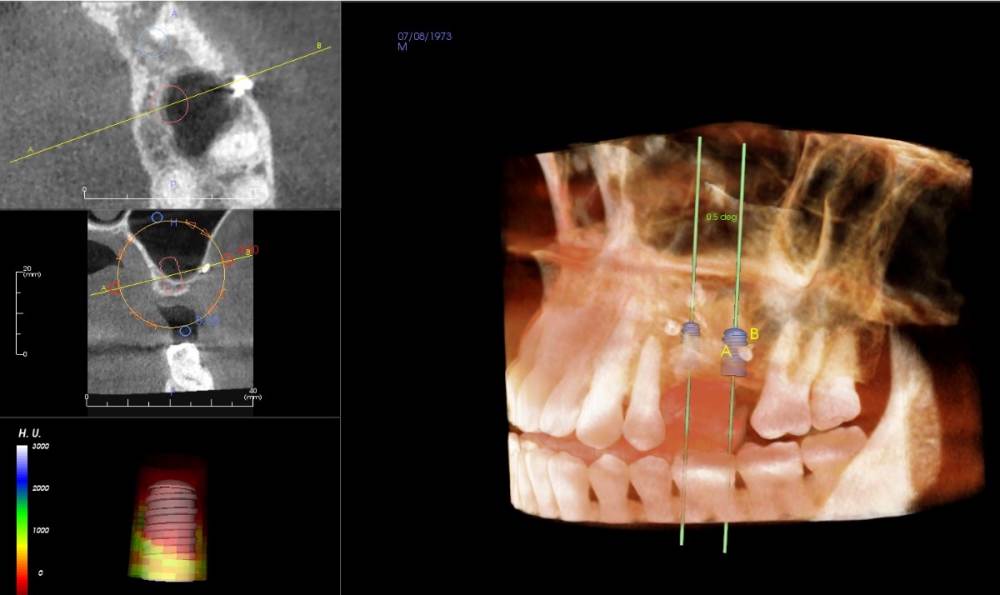

Smut Опубликовано 24 ноября, 2021 Автор Поделиться Опубликовано 24 ноября, 2021 https://drive.google.com/drive/folders/11eojiqr5oxV2DyflrsOpWAdLUCzuzkTC?usp=sharing Ссылка на комментарий

Irouil Опубликовано 24 ноября, 2021 Поделиться Опубликовано 24 ноября, 2021 В области отсутствующего 5-го зуба Вам ранее проводилась костная пластика, оценка состояния тканей после ее проведения должна происходить уже при раскрытии раны, но на снимке все выглядит хорошо. Как давно Вам проводили эту операцию? В области отсутствующего 6-го зуба действительно потребуется синус-лифт, при латеральном доступе («открытом» варианте операции) действительно нужно создать дополнительное окно, но не все хирурги укрывают это окно мембраной и данная операция не преследует цель восстановления костной стенки в области данного окна - так как синус лифт чаще всего проводится по верхней край окна, то костная ткань чаще всего вырастает внутри пазухи практически «заподлицо» со сформированными краями и никаких значимых последствий наличие подобного окна не имеет при определённом навыке в Вашем случае вполне возможно провести синус лифт крестальным доступом, то есть прямо через дырку, просверленную для импланта 1 1 Ссылка на комментарий